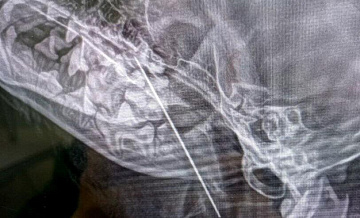

В Москве ветеринары достали из собаки швейную иглу

ПРОИСШЕСТВИЯ

28 января 2025 481

Ветеринары из Москвы извлекли большую швейную иглу из десятимесячной йоркширской терьерши Маруси, которая страдала от непрерывного кашля.